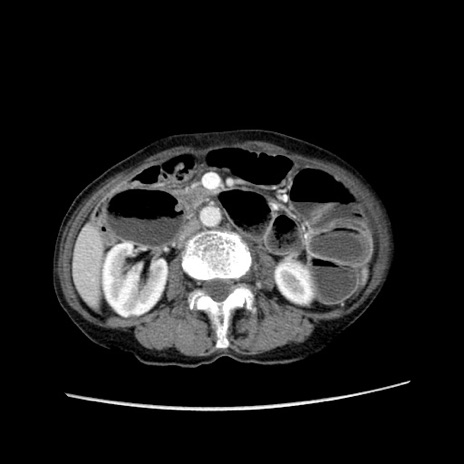

症例25(横断像)

【症例】80歳代女性

【主訴】胸のつかえ感

【現病歴】約9時間前に食後から胸のつかえた感じあり、嘔吐あり、来院。

【既往歴】胃癌(全摘)、胆摘、虫垂炎

【身体所見】心窩部に圧痛あり、反跳痛なし。

【データ】WBC 5700、CRP 0.05